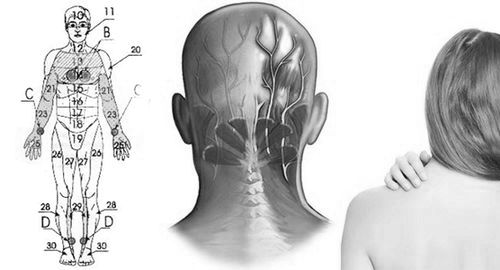

Локалізація болю, супутні симптоми, а також подальше лікування захворювання залежить від того, в якому місці була поразка нерва. Зазвичай це шийний, грудний або поперековий відділи хребта. Саме тому розрізняють кілька видів захворювання, які характеризуються специфічними симптомами і методами лікування.

Крім зазначених видів невралгії, дивуватися можуть також сідничний нерв (в результаті вагітності, радикуліту або підняття тяжкості) і потиличний нерв.